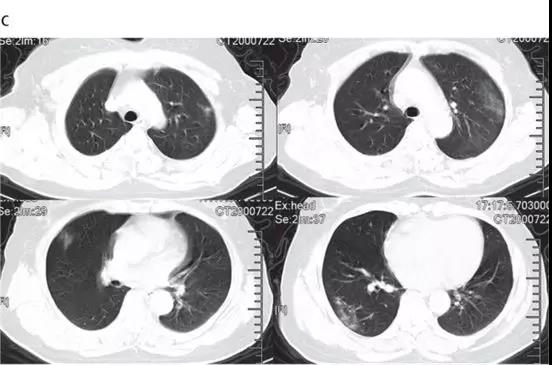

随后的胸部CT显示双侧毛玻璃样混浊,而实变消除(见下图)。